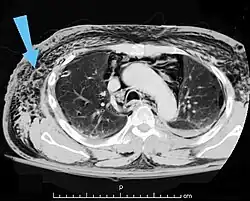

Verletzungen der Lunge können neben einer Lungenkontusion als Quetschverletzung Lungenrisse sein. Letztere führen zu einem Pneumothorax, wie er bei 10 bis 50 Prozent der Patienten mit Thoraxtrauma auftritt,[6] und gegebenenfalls zu einem Spannungspneumothorax. Blutungen in den Thorax hinein führen zu einem Hämatothorax. Bei einem Hämatopneumothorax treten sowohl ein Pneumo- als auch ein Hämatothorax in Kombination auf. Symptome sind zunächst Luftnot und je nach Ausmaß der Blutung auch Kreislaufinstabilität. Bei einem Pneumothorax kann sich insbesondere bei Ausbildung eines Spannungspneumothorax ein Hautemphysem bilden, das eine große Ausdehnung erreichen kann. Therapie ist eine Entlastung der Pleurahöhle mittels Thoraxdrainage auf der betroffenen Seite. Üblicherweise kommen kleinere intrathorakale Blutungen von alleine zum Stehen, so dass außer einer Drainage keine weiteren Maßnahmen notwendig werden. Eine Thorakotomie zur operativen Blutstillung kann bei einem initialen Blutverlust von mehr als 1.500 ml nach der Thoraxdrainage oder bei einem fortwährenden Blutverlust von mehr als 250 ml pro Stunde über mehr als vier Stunden erfolgen.[2][5]